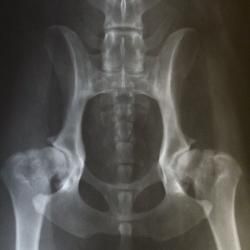

Hunden bedøves let, lægges på ryggen med benene strakt helt ud, og der tages et røntgenbillede af dens hofteled i denne position.

Hunden får tildelt en HD-vurdering efter følgende skala: A,B,C,D,E, hvor A står for HD-fri og E står for svær HD.

Hunden skal være mindst 1 år gammel ved fotografering. For gigantracerne gælder dog, at de skal være fyldt 1½ år.